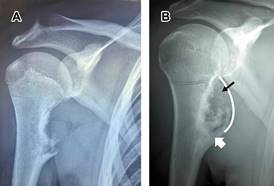

Las radiografías muestran una lesión exofítica con continuidad corticomedular con el hueso adyacente (Figura 1), con base de implantación sésil o pedunculada. La ecografía visualiza la capa cartilaginosa como un área hipoecoica sobre la corteza ósea, la tomografía computarizada (TC) permite visualización de la continuidad corticomedular de la lesión (Figura 2), la resonancia magnética (RM) es de elección para valorar las estructuras circundantes a la lesión, la capa de cartílago no mineralizada muestra señal alta en T1 y T2 (Figura 3). La resección está indicada al final del crecimiento.

Figura 1: A) Radiografía anteroposterior de hombro derecho en adolescente de 17 años, muestra exostosis osteocartilaginosa en metáfisis de cara interna. B) Línea blanca delimitando la masa ocupativa, área cartilaginosa (flecha negra) y área calcificada (flecha blanca).